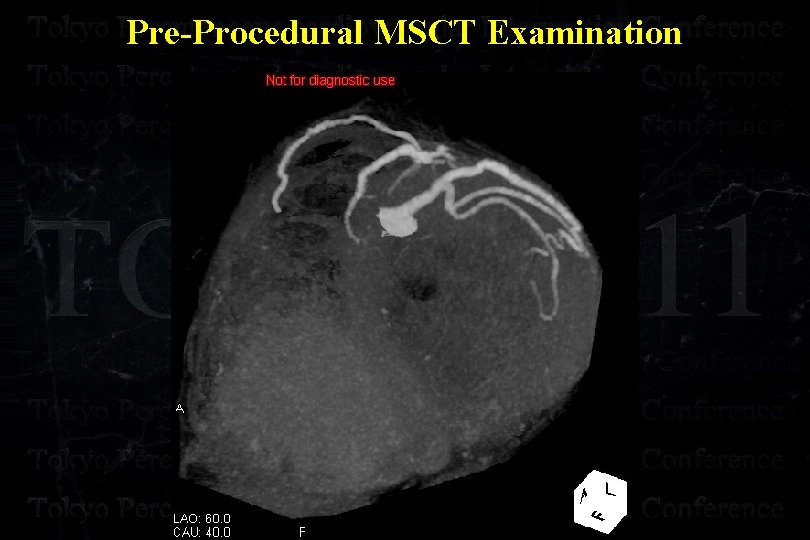

Pre-Procedural MSCT Examination

Pre-Procedural MSCT Examination